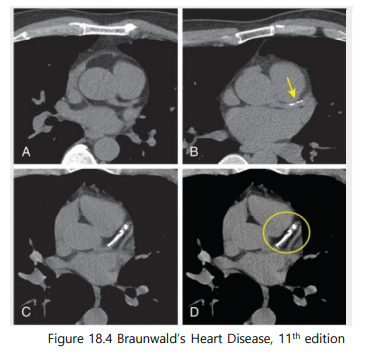

요즘 혈액순환도 안 좋고 나이도 드는데…혈관이 걱정이에요.최근 언론을 통해 다양한 건강 관련 보도가 나오면서 본인의 혈관동맥경화를 걱정하는 분들이 많이 계십니다. ^^ 내 혈관의 동맥경화는 어떻게 알 수 있습니까.대표적인 검사를 소개하자면 ① 심장혈관 CT(아래 그림) ② 경동맥 초음파(아래 그림) ③ 혈관경직도검사(ABI, PWV)에서는 검사가 있습니다.

심장칼슘 CT(coronary calcium score)가 무엇입니까?심장혈관에 칼슘이 얼마나 쌓여 있는가는 보는 검사에서 CT상 하얗게 보이는 부분입니다.(심장조영술과는 다릅니다. 심장혈관조영술은 조영제를 넣어 혈관을 직접 보는 시술로 보다 정확하지만 고위험 시술입니다.)

심장혈관조영술과는 다른 검사주의 CA Cscore (Agatstonscale) 뜻0 혈관에 칼슘침착이 없음1-10lowrisk 심장혈관질환 위험도 10% 미만 11-99 약간의 혈관칼슘침착 100-399 중등도 혈관칼슘침착 400-999 심각한 혈관칼슘침착 1000+1년 내에 심장혈관질환 발생확률 25% 이상 Q. AHA/ACC cholesterol guideline (2018)

40-75세 사이 LD Lcholesterol이 70-190인 경우 (or ASCVD 77.5-<20% Intermediaterisk의 경우) 심장칼슘 CT를 촬영하여 치료방향 설정에 도움을 줍니다.

- CAC=0→Nostatinunless DM, Smoking, FHx: “Power ofzero”: 약을 사용하지 않고 볼 수 있다.2) CAC=1-99 (Mildcalcium deposit)→statin약을 먹는 것이 좋다 3) CAC100100 and / or 7575th percentile → statin약을 빨리 사용하라

- 최근 다양한 권고안에서는(Circulation. 2019; 140: e596 – e646/European Heart Journal (2021) 42,32273337) 심장칼슘 CT를 경동맥 초음파에서 권장하는 경향이 관찰됩니다.